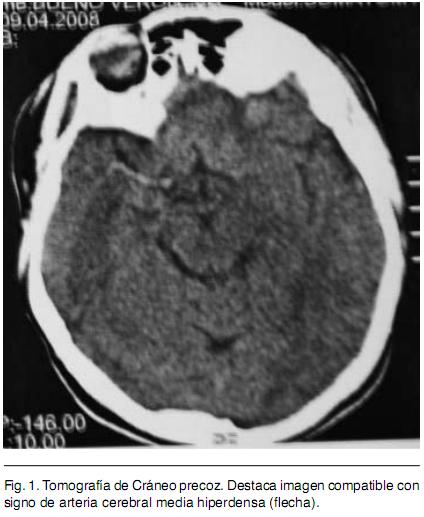

Sexo femenino, 22 años, procedente de medio urbano, diestra, educación primaria completa. Antecedente de migraña de larga data, sin cefalea durante los últimos meses. Destaca en lo ginecobstétrico el consumo de anticonceptivos orales (ACO) combinados y de baja dosis hasta hace tres meses en que se inicia administración de anticonceptivos combinados por vía intramuscular mensual. Dos gestas, dos cesáreas, con nacidos vivos sin complicaciones neonatales; niega historia de aborto espontáneo. Quince días previos a la consulta instala en forma brusca síndrome focal neurológico caracterizado por hemiplejia izquierda total y disartria parética; precediendo al mismo cefalea de predominio en hemicráneo derecho. Se inicia valoración en centro de segundo nivel y se envía en la evolución para completar la misma en centro de referencia. Se realiza Tomografía Computada (TC) de cráneo que informa imagen compatible con ACV isquémico de territorio silviano derecho (Figura 1). Se completa valoración con Resonancia Nuclear Magnética (RNM) que evidencia infarto isquémico en etapa subaguda en territorio superficial y profundo de arteria cerebral media (ACM) derecha, asocia imagen compatible con trombosis de la ACM. El electrocardiograma (ECG) evidencia un ritmo sinusal (Figura 2), con frecuencia de 75 latidos por minuto, P y P-R normales, ventriculografía normal. El Ecocardiograma transtorácico no evidenció alteraciones anatómicas ni trombos en cavidades cardiacas, la Fracción de Eyección del Ventrículo Izquierdo fue de 65%. El Eco Doppler de vasos de cuello informa oclusión de carótida interna derecha de reciente evolución. Arteriografía de cuatro vasos de cuello evidencia disección de carótida interna derecha en el origen y oclusión de ACM derecha en el origen (Figura 3). De la analítica de laboratorio general destaca hemograma, hepatograma, azoemia y creatininemia normales. HIV y VDRL no reactivos. Velocidad de Eritrosedimentación 4 mm en la primera hora. De la valoración de factores de riesgo cardiovascular destaca: Lipidograma con colesterol total de 200 mg/dl, LDL 128 mg/dl y HDL 49 mg/ dl. Glicemia y uricemia normales. Del estudio de la crasis y factores protrombóticos destaca: Tiempo de protrombina de 85%, KPTT 27 segundos, Fibrinógeno 321 mg/dl. Factor V Fig. 1. Tomografía de Cráneo precoz. Destaca imagen compatible con signo de arteria cerebral media hiperdensa (flecha). Fig. 2. Resonancia Nuclear Magnética. Permite valorar imagen compatible con Infarto de territorio superficial y profundo de Arteria Cerebral Media. Fig. 3. Arteriografía de vasos de cuello. Permite visualizar imagen característica de disección arterial (flecha). de Leiden, variante termolábil del gen Metiltetrahidrofolatoreductasa (MTHFR) y FII 20210A, ausentes. Anticuerpos antifosfolipidicos negativo. Del laboratorio de inmunología destaca: Anticuerpos Antinucleares (ANA) 1/40.